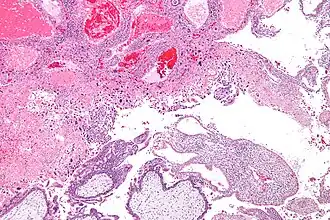

Трофобластическая болезнь (от греч. trophe — пища, питание и blastos — росток, зародыш) — заболевание, в основе которого лежит нарушение развития и роста трофобласта, сопровождающееся последовательными морфологическими изменениями от пузырного заноса до хориокарциномы с соответствующими биологическими и клиническими признаками. Проявляется тремя основными формами: синцитиальным эндометритом, пузырным заносом и хорионэпителиомой. Заболевание чаще всего встречается в Юго-Восточной Азии и островах Тихого океана и относительно редко — в Европейских странах и США. Уникальность данного заболевания в том, что эти опухоли представляют собой аллотрансплантанты, которые возникают в момент зачатия и в случае злокачественной трансформации происходит прорастание в ткани материнского организма, а также метастазирование.